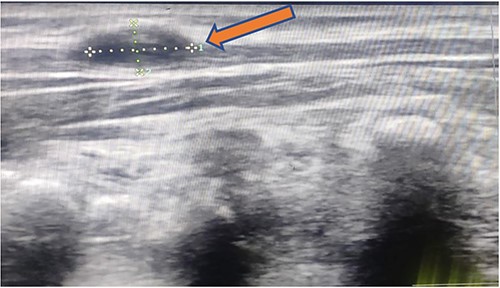

X-ray chest and dorsal spine seemed within normal limits (Fig. 2). Ultrasonography (USG) of the mass revealed an anechoic 1.8 × 1.2 cm lesion with no internal vascularity or calcification (Fig. 3). It was found to be in the subcutaneous plane with a minor extension to the muscular plane over the mid-upper back region, giving it an impression of a nerve sheath tumor. The hemogram was within normal limits. At this stage, we had a differential diagnosis of a nerve sheath tumor in mind.

1.8 × 1.2 cm anechoic lesion in the subcutaneous plane with a small intramuscular extension.